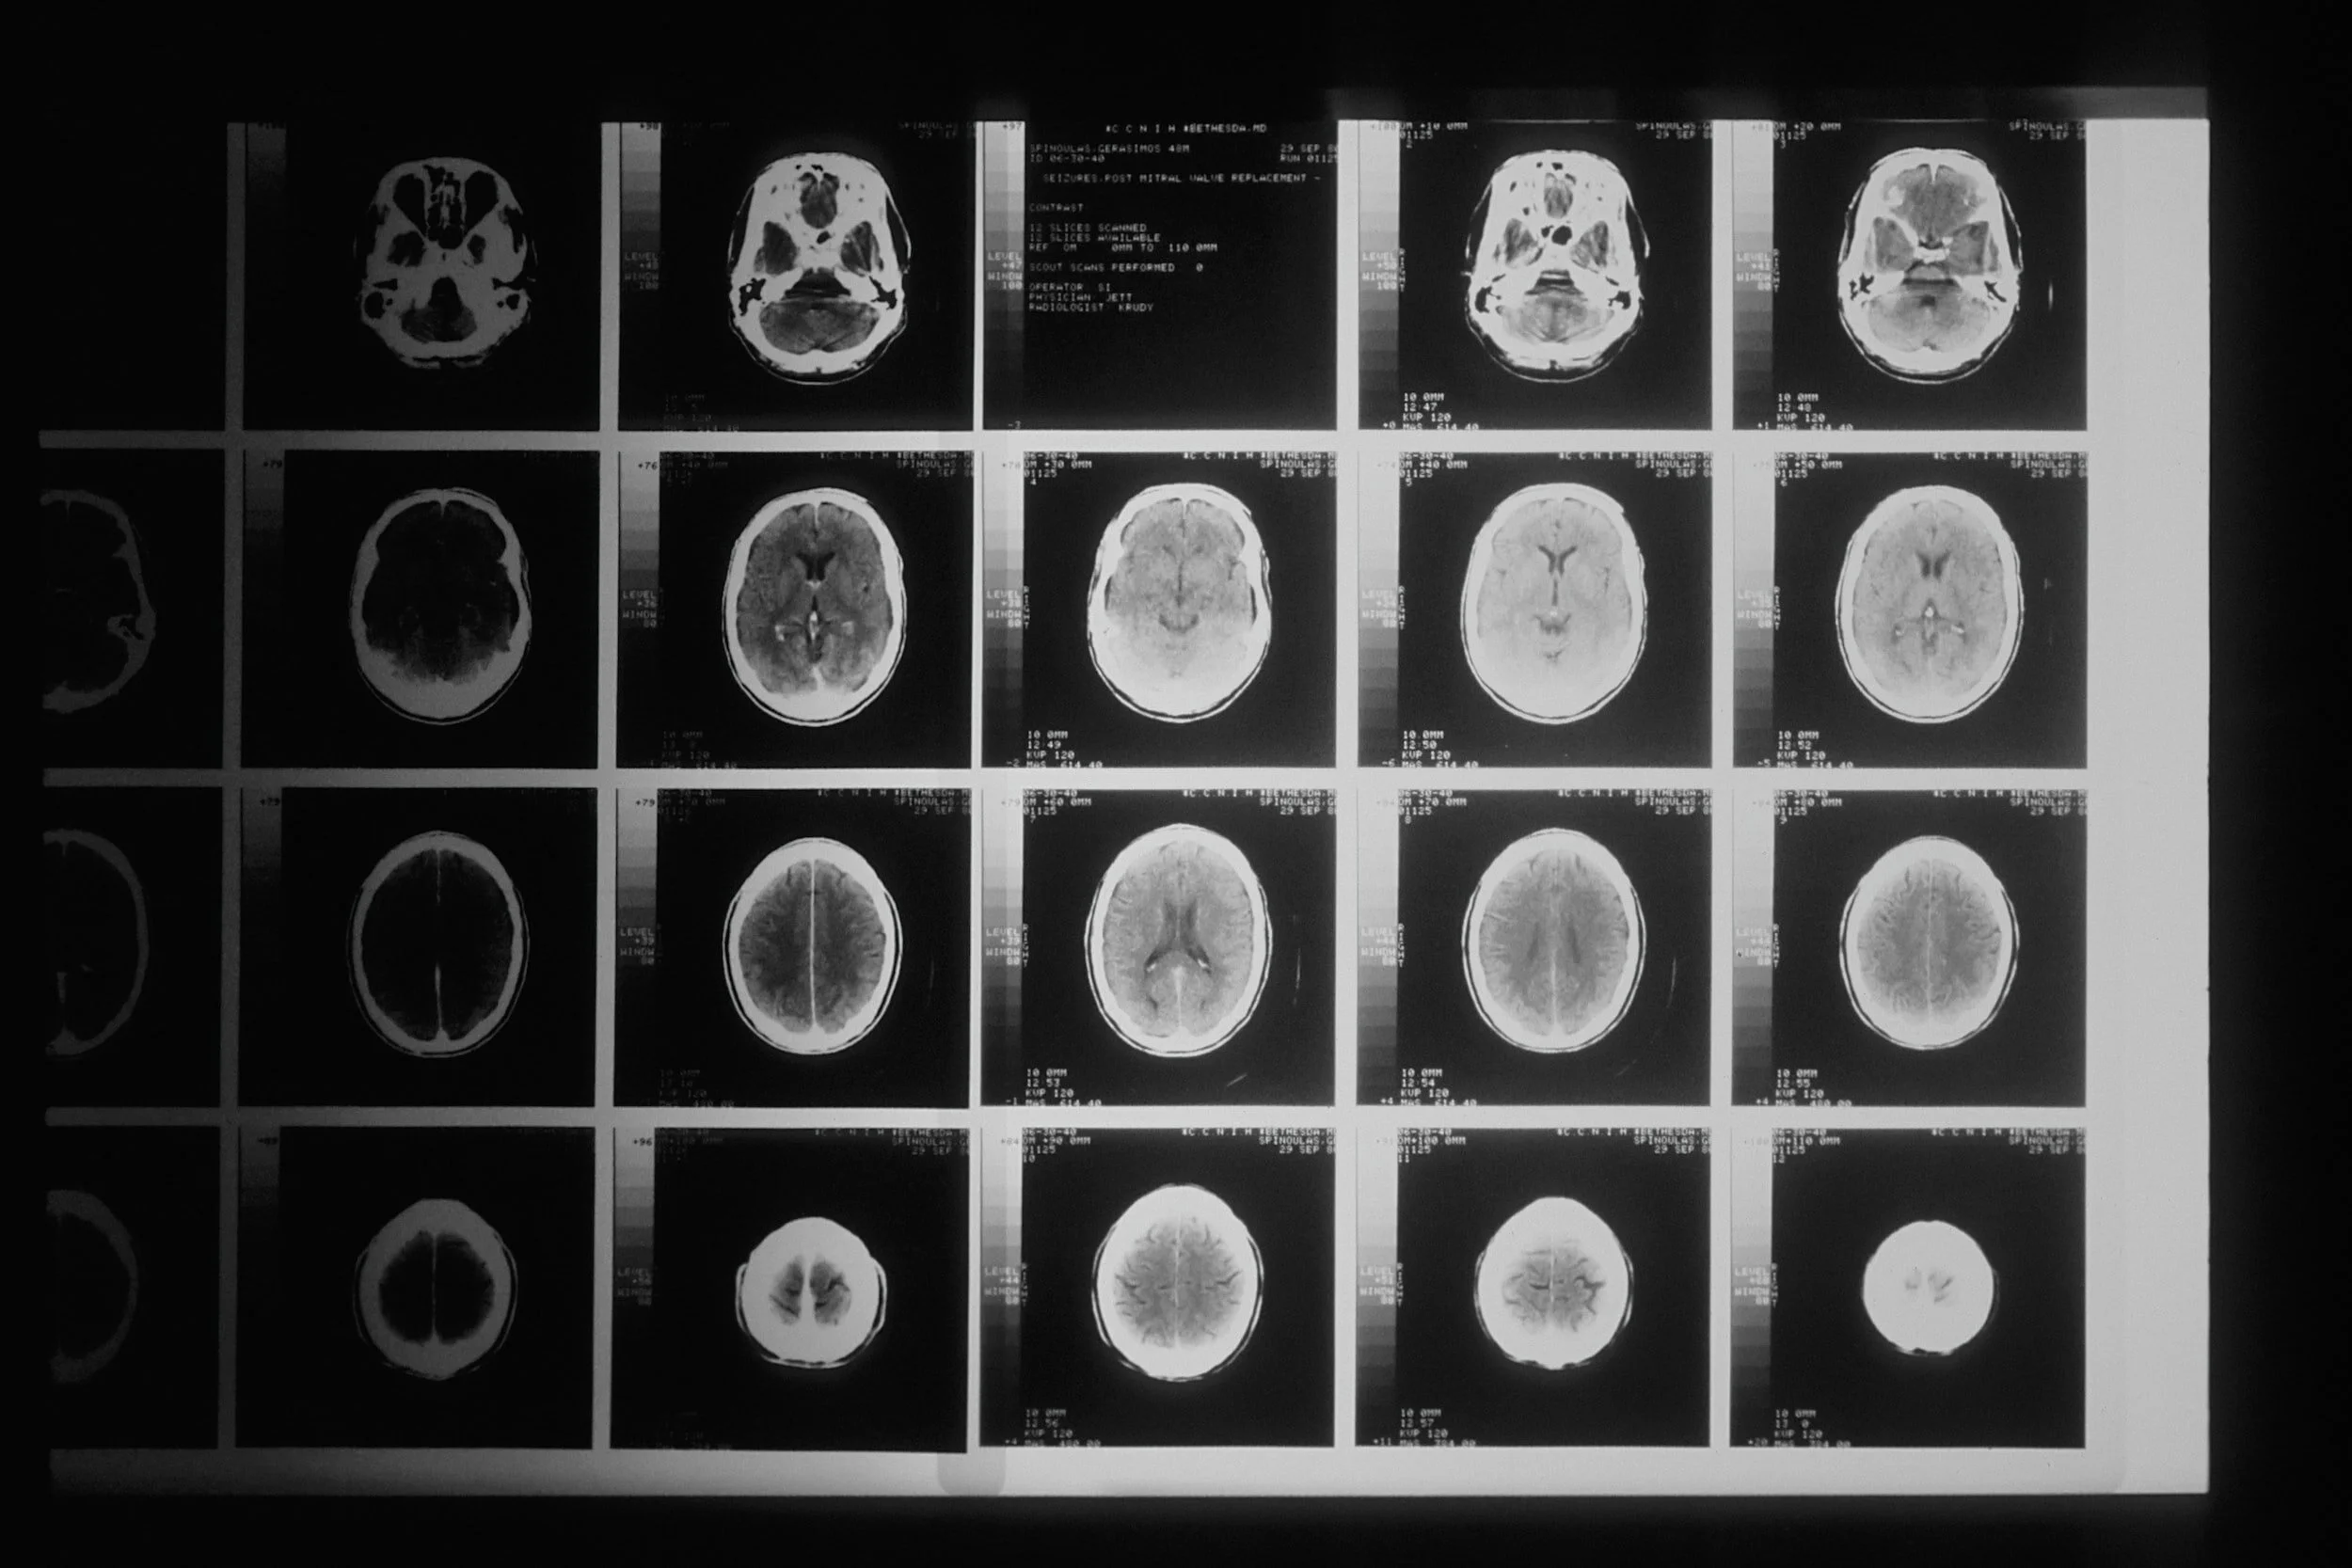

Stroke affects millions of people worldwide every year. Our goal is to understand the mechanisms underlying stroke and to develop new and effective treatments to prevent and treat this devastating condition.